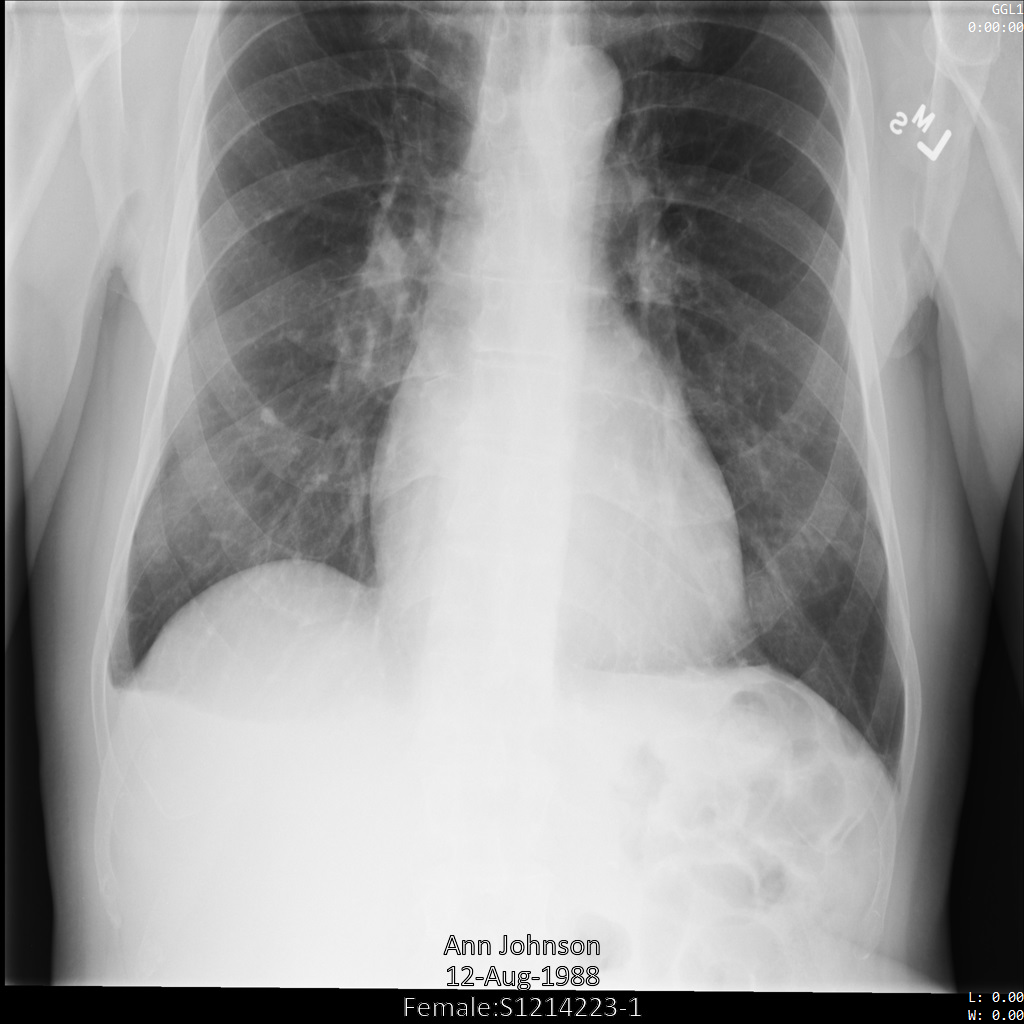

Nachdem das Bild mit der Option REDACT_ALL_TEXT an die Cloud Healthcare API gesendet wurde, sieht es so aus: Während der eingebrannte Text unten im Bild entfernt wurde, bleiben die Metadaten in den oberen Ecken des Bildes erhalten. Informationen zum Entfernen der Metadaten finden Sie unter De-identify-DICOM-Tags.